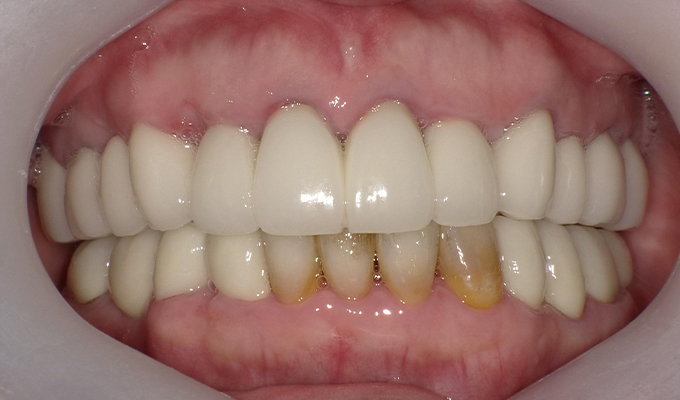

case1インプラントとメタルボンドブリッジの症例

初診時(2010年)

初回メンテナンス時(2014年)

最新メンテナンス時(2024年)

- 初診時の年齢

- 60代女性(2010年)

- 主訴

- ちゃんと咬めるようになりたい。最近孫が生まれたから一緒に歌ったりしたいけど、今は歌うこともできないから・・・・。と

- 治療内容

- 5年ほど前に入れ歯を作ったそうですが合わなかったので使用してなかったせいか前歯がグラグラになっていて今にも抜けそうな状態でした。

保存が難しい歯を抜歯し、上はインプラント8本、下は奥歯にインプラント4本埋入しました。

補綴は変色しないメタルボンドを選択されたので治療完了して11年経過してもとてもきれいな状態で維持されています。

初診時にお話しされていたお孫さんも中学2年生になったそうで、歯の治療をしたおかげで充実した毎日が送れてます、とメンテナンス時もいつも嬉しそうにされています。